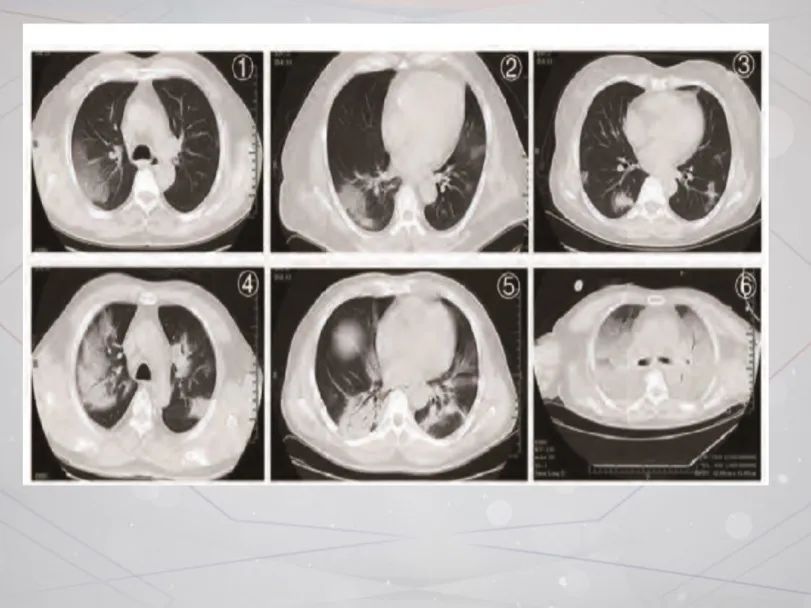

【医学生日记】重症新冠肺炎患者典型"大白肺"

下图是新冠肺炎患者在做肺部ct时的图像,肉眼可见的红色圈内或白色

新冠病毒是如何攻击患者肺部的?8张影像图给了答案